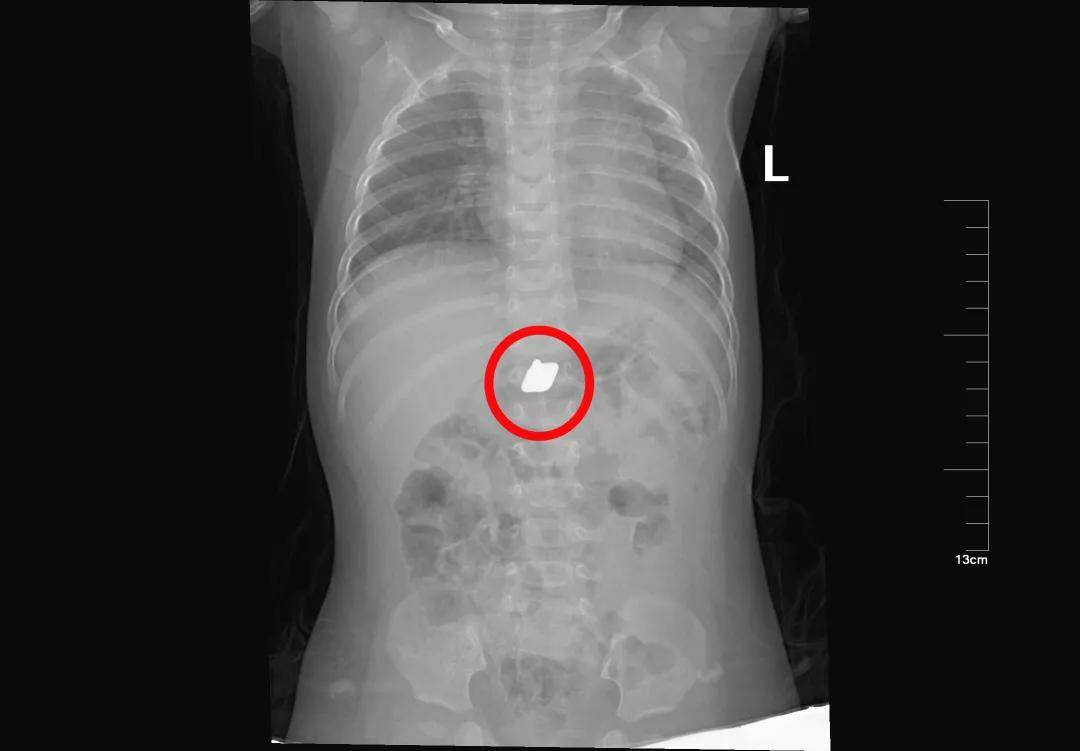

硬币的一场“旅行”

硬币是儿童消化道异物中最最最常见的。虽然有些孩子可以自行排出,但是部分幼龄患儿仍需手术取出。家长还是当心点吧!

进入胃啦